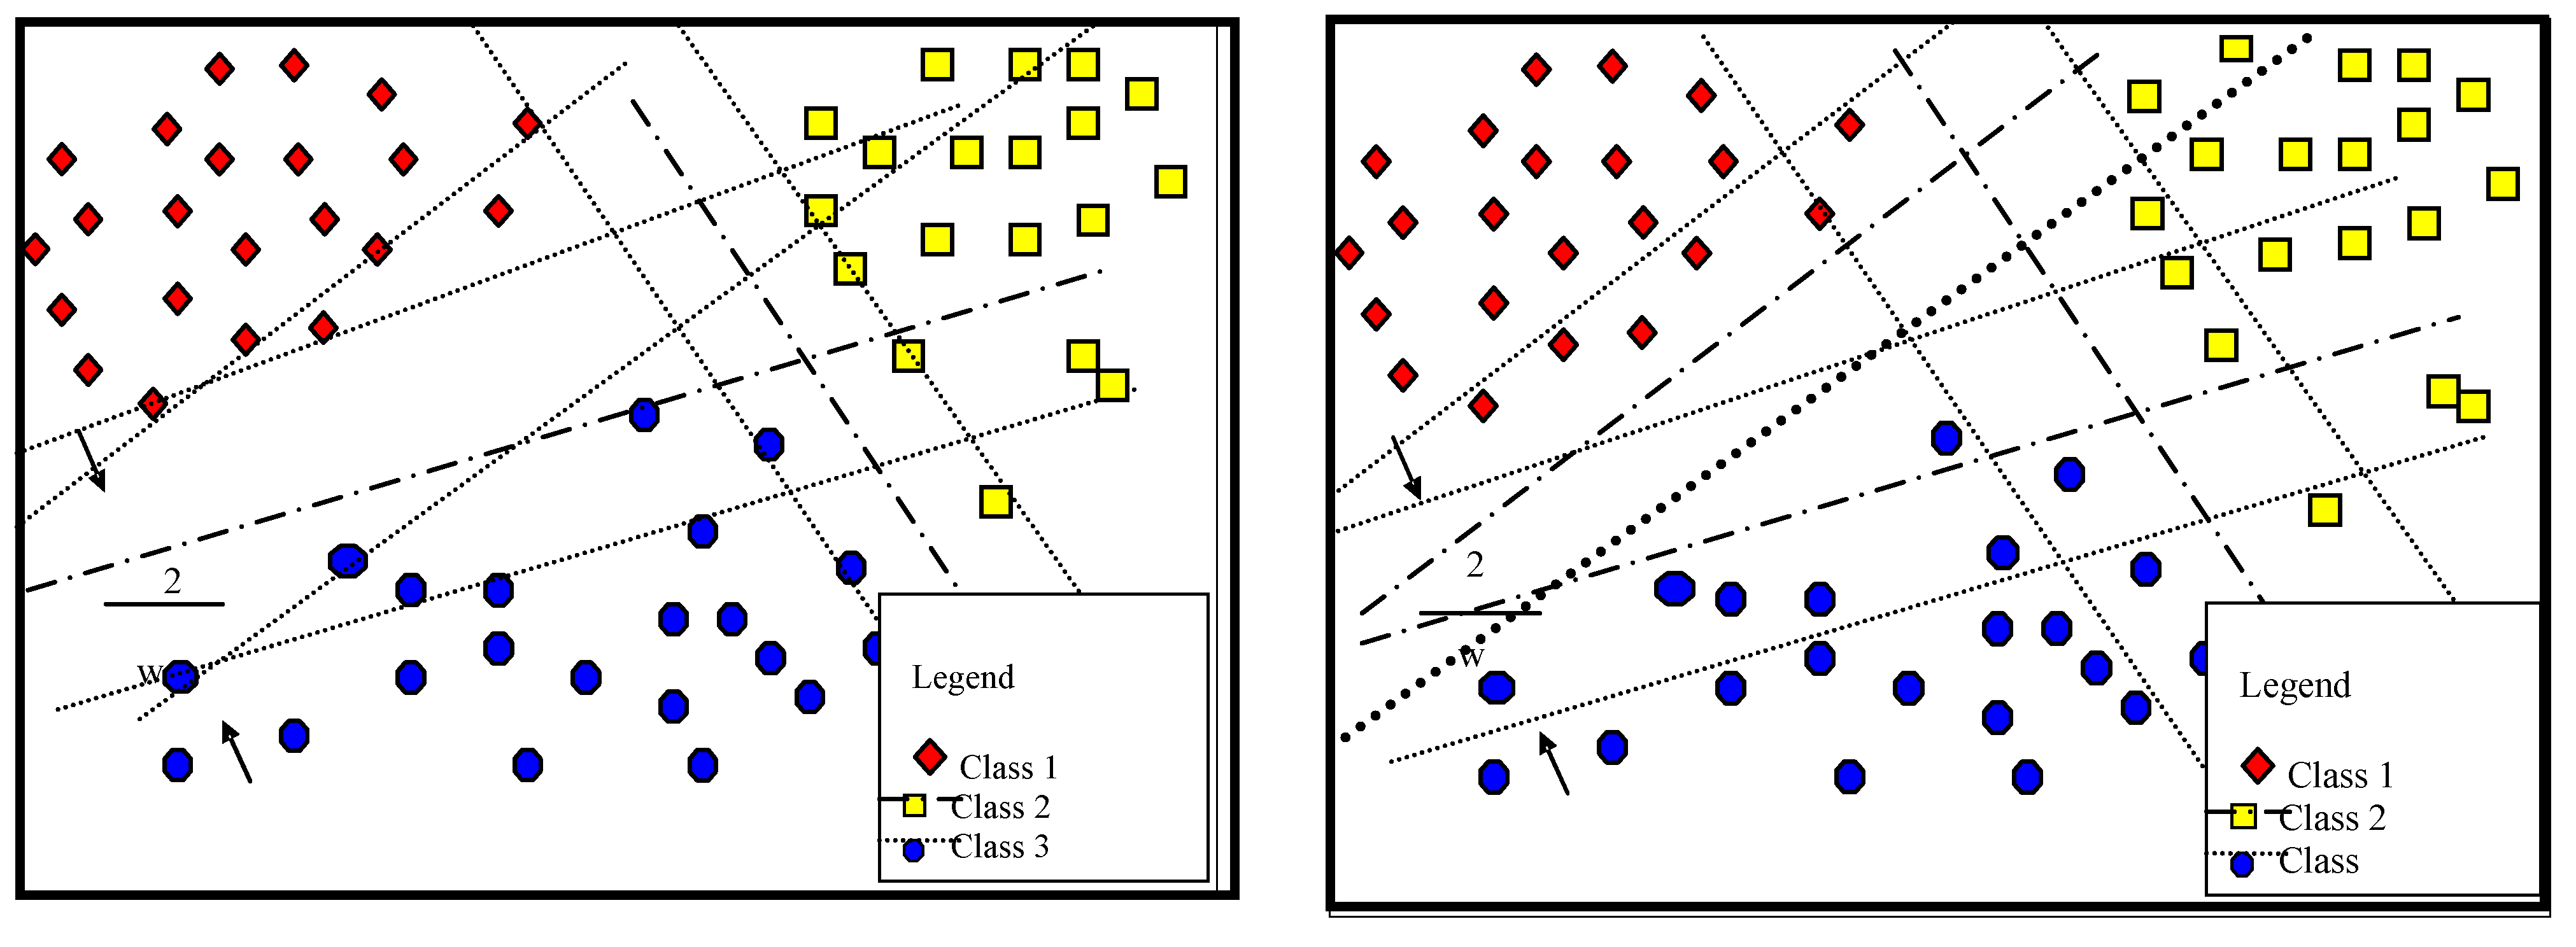

2. Multi-Classification LS-SVM Survey

3. Proposed multi-classification WP-SVM

3.1. Proposed Multi-Classification

3.2. Proposed WP-SVM